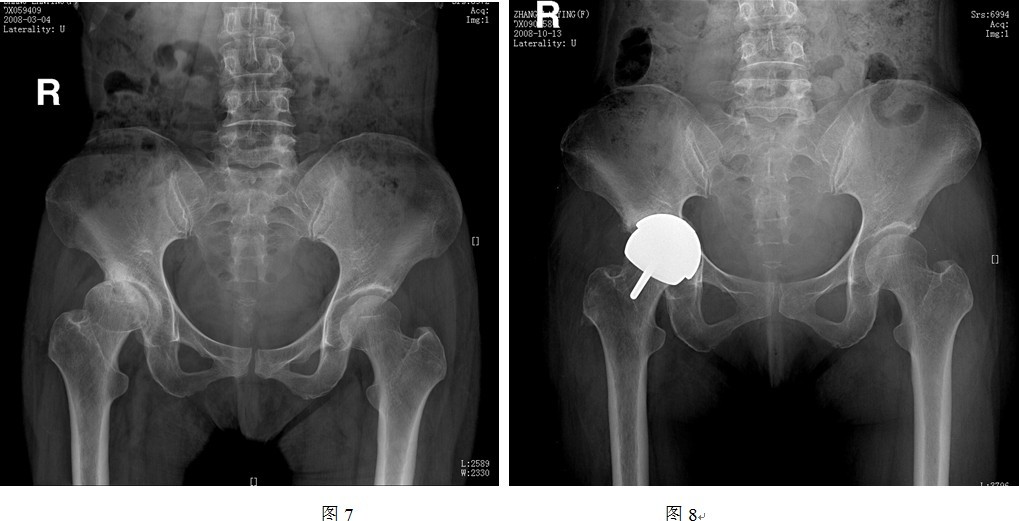

(1)头和臼假体之间有时很难良好匹配

DDH患者的髋臼发育不规律,头臼的匹配程度远远差于正常髋关节,而THRA的头臼假体间是一对一大小匹配,所以对于发育偏小的髋臼,按照髋臼侧决定THRA假体套件大小会出现股骨头过度磨锉,造成切迹;而按照股骨侧决定假体套件大小则会造成髋臼过度磨锉,大量骨质丢失,影响稳定性(图7、8所示即为以股骨侧决定假体大小时,髋臼侧出现过度磨锉,以致锉穿髋臼底部)。同样道理,对于发育偏大的髋臼,按照髋臼侧选择假体大小会造成人为的股骨颈缩窄(图9中所示病例以髋臼侧决定假体大小,导致股骨侧假体过大,反衬出股骨颈细小),而按照股骨侧决定假体型号则可能会出现髋臼软骨磨锉不充分,也可能影响髋臼假体稳定性(图10中所示病例以股骨侧选择假体大小,原始髋臼对于臼杯假体相对偏大,臼杯边缘的软骨尚未充分磨锉)。

图中所示右侧髋臼发育较小,股骨头发育扁宽,按照股骨侧决定假体大小,则髋臼侧假体相对偏大,造成髋臼过度磨挫。

图中所示,按照髋臼侧决定假体大小原则,匹配的股骨侧假体较股骨头颈来说偏大,造成人为股骨颈缩窄现象。

图中所示,按照股骨侧决定假体大小原则,匹配的髋臼假体较原始臼来说过小,髋臼磨挫不充分,假体与髋臼匹配不良。